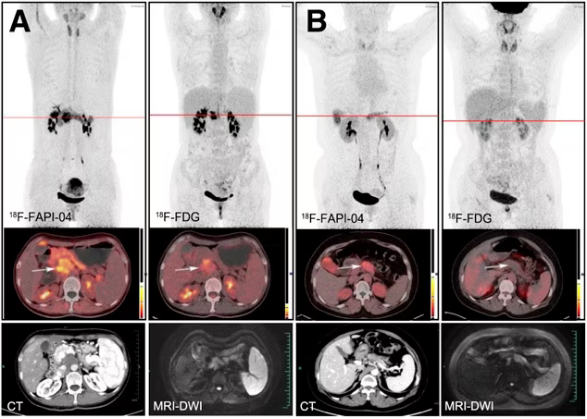

圖示為代表性患者(A和B)中使用兩種放射性示蹤劑獲得的原發腫瘤的典型PET(上)、PET/CT(中)以及CT和MR(下)圖像。腫瘤用箭頭標出。DWI =彌散加權成像。圖片由《Journal of Nuclear Medicine》提供。

根據調查結果,F-18 FAPI-04 PET/CT識別了所有PDAC患者,而F-18 FDG-PET/CT漏診1例。原發性腫瘤 (10.63比2.87,p < 0.0001)、淋巴結轉移(2.9比1.43,p < 0.0001)和遠處轉移(肝臟,6.11比3.1,p = 0.002;腹膜,4.7 vs. 2.08,p = 0.015)中,F-18 FAPI-04示蹤劑攝取均高于F-18 FDG。